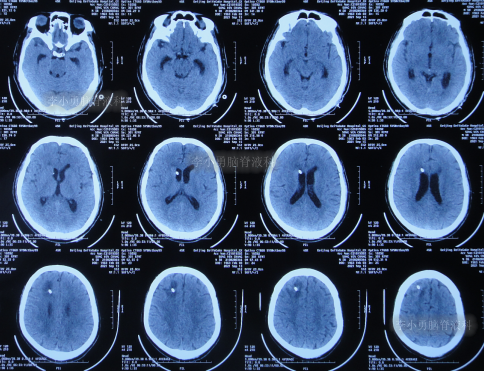

2021年8月28日(第1家医院第3次治疗12天后),出现脑积水(图-2)。

图-2:2021年8月28日头颅CT